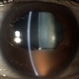

- SD OCT of 32-year-old woman two weeks after vitrectomy. Round SRF was found. VA 20/50.